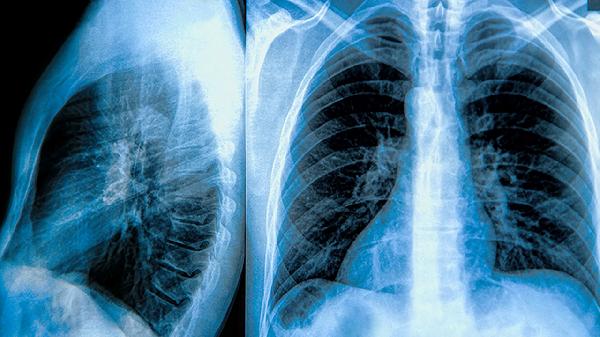

1、肺大泡与气胸复发的关系密切。肺大泡是肺组织局部过度膨胀形成的薄壁囊腔,容易破裂导致气胸。未手术的肺大泡患者,气胸复发率显著高于手术患者,复发次数越多,肺功能损害越严重,甚至可能发展为慢性气胸。肺大泡的形成与吸烟、慢性阻塞性肺疾病、先天性肺发育不良等因素有关,及时手术切除肺大泡是预防复发的关键。

2、手术治疗是降低气胸复发率的有效方法。胸腔镜手术是目前首选的治疗方式,创伤小、恢复快,可精准切除肺大泡并进行胸膜固定。开胸手术适用于复杂或广泛性肺大泡,可彻底切除病变组织。化学胸膜固定术通过注入硬化剂使胸膜粘连,减少复发风险,但可能引起胸痛、发热等并发症。手术时机应根据患者年龄、肺功能、复发次数等因素综合考虑。